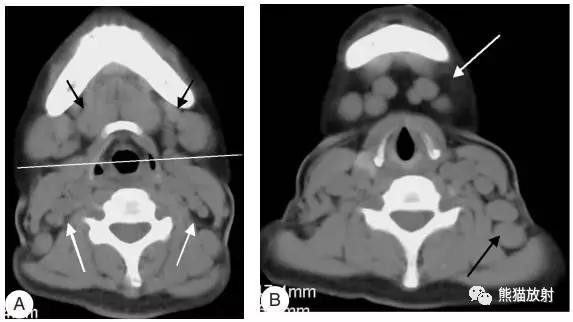

女性,45岁,淋巴瘤。(A)黑箭显示双侧IB区淋巴结,白箭显示ⅡA区淋巴结。(B)白箭显示ⅠA区淋巴结,黑箭显示左侧Ⅴ区淋巴结。